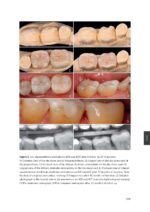

With the advancements in material science, adhesive dentistry, and industrial technologies, restorative dentistry has become a dynamic field. Its goal is to restore damaged teeth to their natural form and function. Regular updates in concepts, including preparation type, material choice, and adhesion protocols, are required. Damaged teeth with substance loss due to dental caries or trauma can either be restored with full coverage crowns (extracoronal) or partial restorations (intracoronal). Tooth preparations for partial restorations can be classified as either an inlay, which involves no cusp coverage, an onlay, which covers of one or more cusps, or an overlay, which covers all cusps